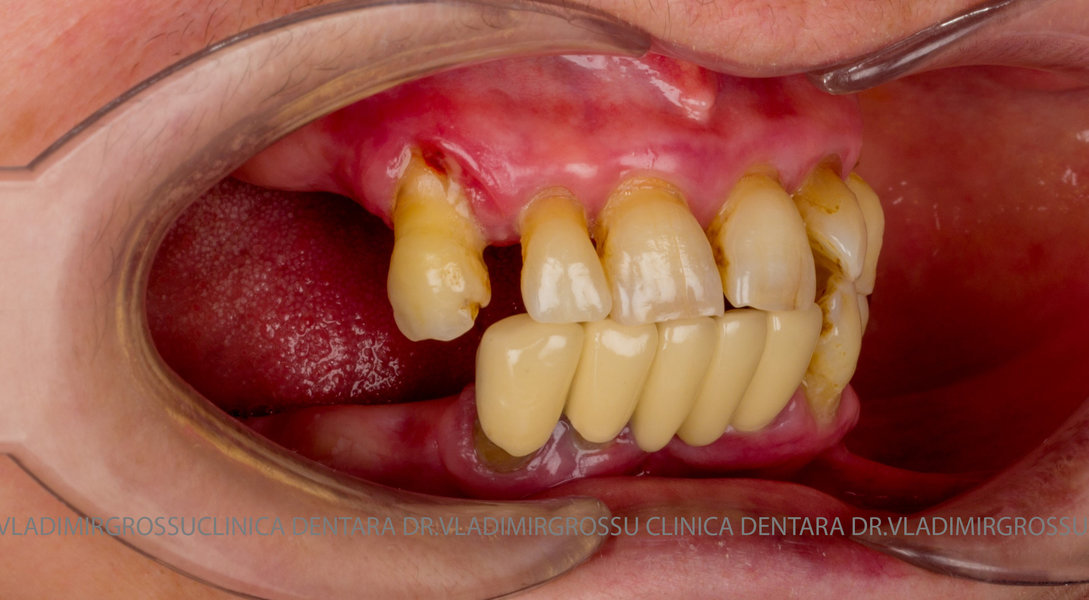

Cazuri clinice conceptul All-on-6